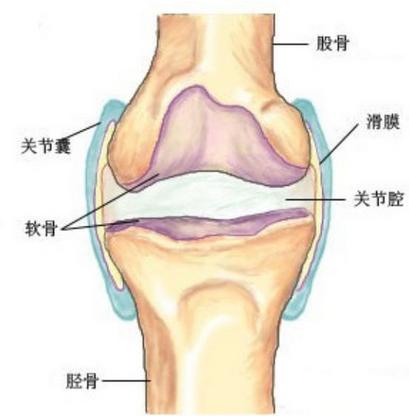

危害一:关节强直变形。患者在病况的前期就会呈现劳累关节生硬活动不灵敏的风湿关节炎的表现,但通常有许多患者不能及时的采纳有效的医治,会使患者的关节遭到完全的破坏,关节变形,所以患者一定要争夺及时的医治,不然等关节发作变形今后就很难再改变了。

危害二:损失关节功用。关节由于长时间遭到炎症的影响,会使关节软骨不断的遭到侵蚀,关节周围的安排被炎症渗出物粘连在一起,座椅所以患者关节的功用就会损失,给患者的生活带来不便。

危害三:肌肉迅速老化和生硬。由于患者的血液循环不晓畅,致使肌肉或者安排所需求的养分无法经过血液循环来运送,所患者关节周围的肌肉就会由于缺乏养分而快速的老化和生硬,所以患者一定要及时的采纳类风湿关节炎的医治,及时的控制住自己的病况开展,及时的得到康复。

危害四:肌肉和血管萎缩。许多患者会呈现患肢和健肢不等大的表象,这就是由于病况严重今后患者的肌肉和血管发作萎缩致使的,使患者劳累的关节呈现不正常的改变。